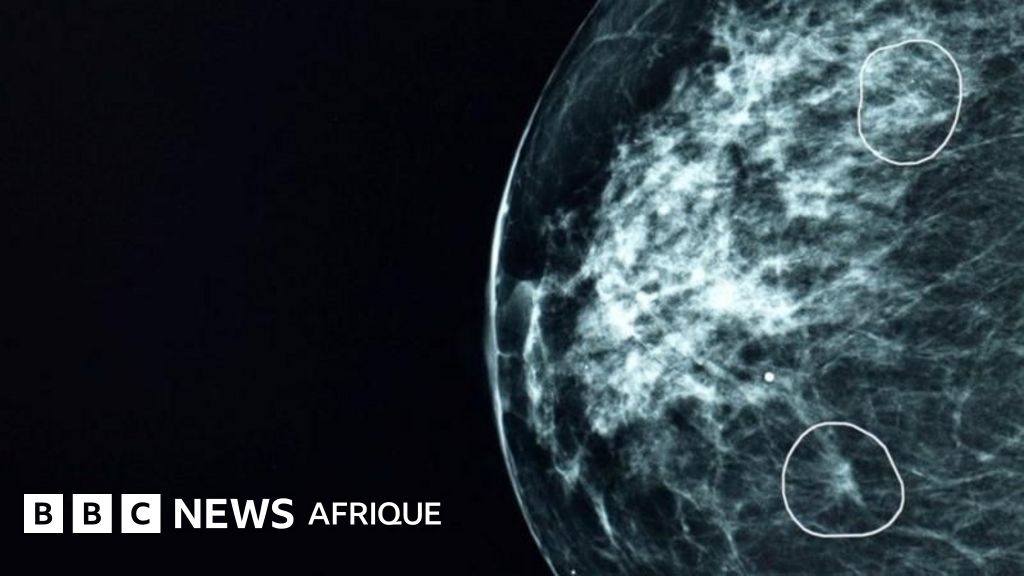

Un outil d’intelligence artificielle (IA) testé dans des hôpitaux britanniques a réussi à identifier de petits signes de cancer du sein chez 11 femmes qui étaient passés inaperçus auprès des médecins.

L'outil, baptisé Mia, a été testé dans plusieurs centres de santé au Royaume-Uni et a analysé près de 10 000 mammographies.

La plupart d’entre eux ne présentaient aucun signe de cancer, mais l’outil a réussi à identifier ceux qui en présentaient, y compris ceux de 11 patients qui n’avaient pas été diagnostiqués par les médecins.

À leurs débuts, les cancers peuvent être extrêmement petits et difficiles à identifier.

La BBC a pu voir l'outil en action à l'hôpital Grampian, témoin de la manière dont des tumeurs pratiquement invisibles à l'œil humain ont été signalées par l'outil.

Ces tumeurs, selon leur composition, peuvent croître et se propager très rapidement.